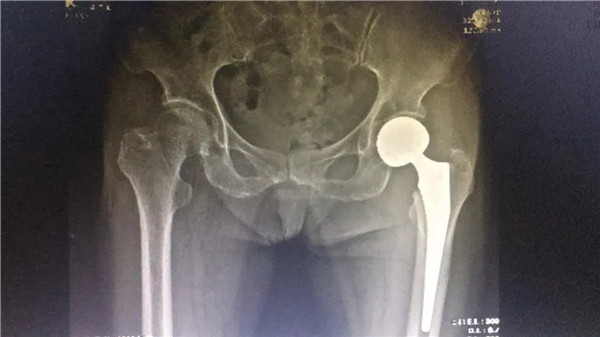

術(shù)前

經(jīng)拍片顯示,陳阿婆左側(cè)股骨頸骨折,須入院手術(shù)治療。一聽要手術(shù),家人便不禁擔(dān)憂起來,這么大年紀(jì)動手術(shù),身體吃得消嗎?危立軍副院長解釋道:高齡病人股骨頸骨折臥床,會導(dǎo)致一系列嚴(yán)重的并發(fā)癥,如疼痛,肺炎、血栓、泌尿系感染等等。隨便哪一項(xiàng)發(fā)生,對病人都是致命打擊,如果病人身體情況不是很差,還是建議進(jìn)行手術(shù),人工關(guān)節(jié)置換,能讓病人盡早恢復(fù)患肢活動,縮短臥床時(shí)間,降低死亡率及其他并發(fā)癥的發(fā)生幾率。在聽了危副院長的介紹后,家人遂即辦理了住院手續(xù)。

髖關(guān)節(jié)置換術(shù)圓滿成功

6月4日,在完善各項(xiàng)術(shù)前檢查,身體狀況符合手術(shù)指征后,陳阿婆接受了左髖關(guān)節(jié)置換術(shù)。手術(shù)由危立軍副院長主刀,一個(gè)半小時(shí)后,手術(shù)圓滿成功。術(shù)后,陳阿婆恢復(fù)良好,一周后,便可以下地行走。術(shù)后半個(gè)月,陳阿婆出院回家休養(yǎng)。

術(shù)后